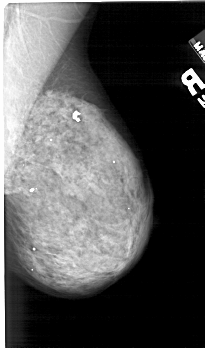

A_1420_1.LEFT_CC

LEFT_CC LINES 5176 PIXELS_PER_LINE 2791 BITS_PER_PIXEL 12 RESOLUTION 43.5 OVERLAY

LEFT_MLO LINES 5461 PIXELS_PER_LINE 2941 BITS_PER_PIXEL 12 RESOLUTION 43.5 OVERLAY

FILE: A_1420_1.LEFT_CC.OVERLAY

TOTAL_ABNORMALITIES 1

ABNORMALITY 1

LESION_TYPE CALCIFICATION TYPE AMORPHOUS DISTRIBUTION CLUSTERED

ASSESSMENT 4

SUBTLETY 2

PATHOLOGY BENIGN

TOTAL_OUTLINES 1

BOUNDARY